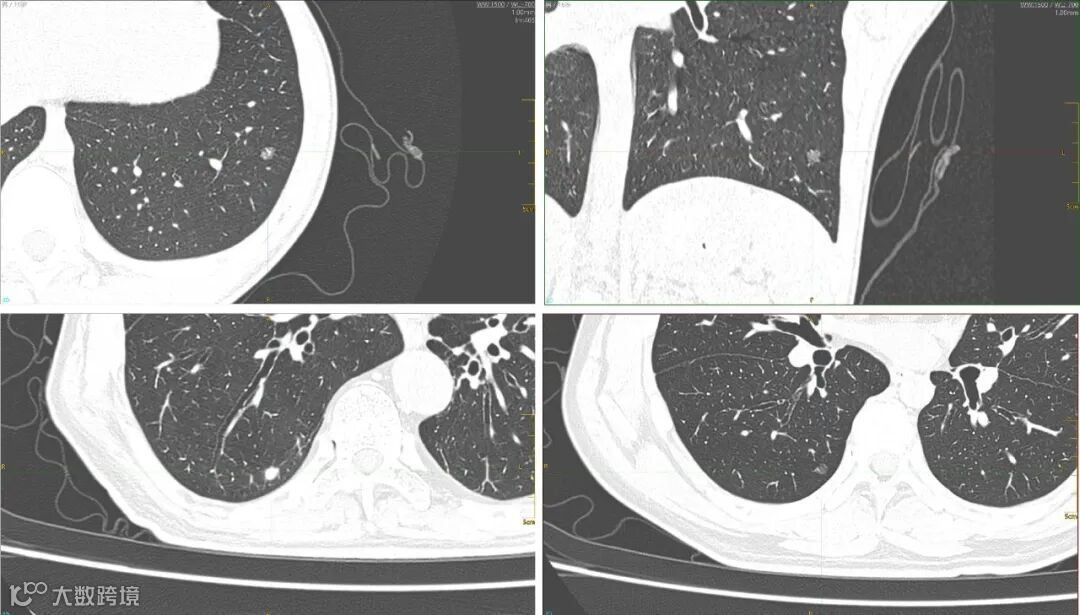

扫描条件:

60kV,100mAs;SFOV:Small;ED:0.09mSv

重建算法:ClearInfinity

同时,针对较低剂量水平下可能造成的细节信息不够、诊断依据不足问题,东软医疗自主研发的CT深度学习重建算法ClearInfinity,可有效避免图像失真,保持原有的纹理信息,搭配1024x1024百万像素重建矩阵,能够4倍提高分辨率,更好地呈现出肺结节结构及边缘影像特征,有效提高微小肺结节的检出率。

肺结节高清显示:ClearInfinity深度学习重建+1024x1024百万像素重建矩阵